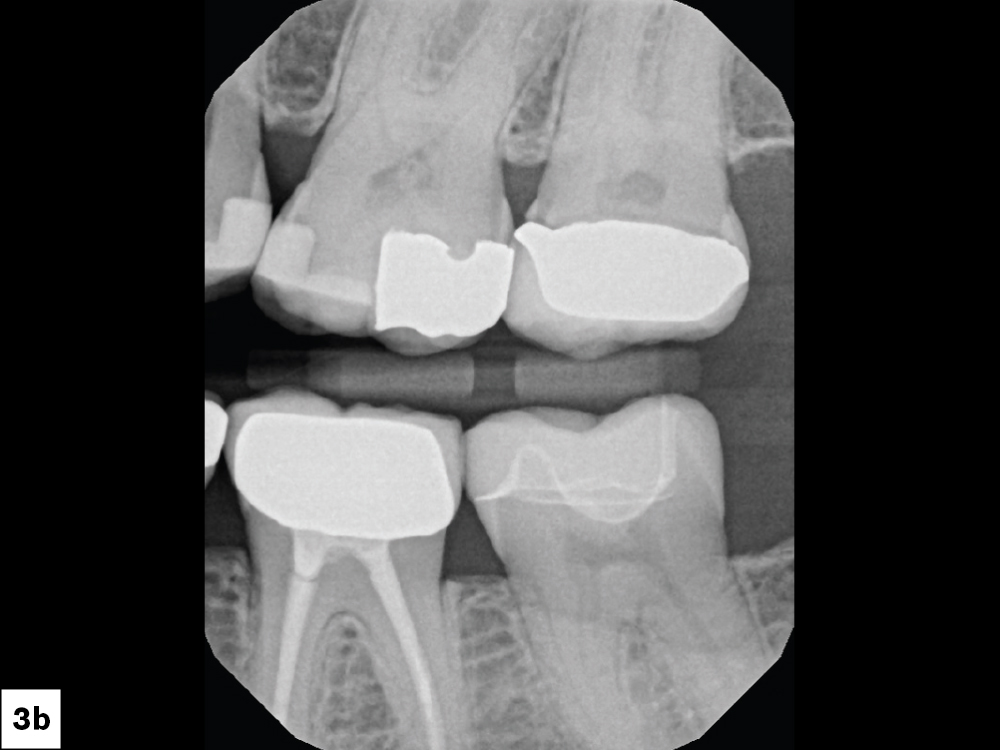

Even though she is a dental hygienist, Nikole decided to wait it out when she was told her crown on tooth #15 had an open margin. But over time, she noticed the area started to shred her floss. That’s when she decided it was time for the crown to be replaced.

Because the patient had high expectations for her restoration, I selected a BruxZir® Esthetic NOW Posterior Milling Block for its combination of esthetics and strength. Though BruxZir Esthetic was originally developed with the anterior in mind, with a yttria content that enhances the overall translucency and color, the material still maintains an excellent flexural strength of 870 MPa, meaning it is sufficiently strong enough to be used anywhere in the arch.